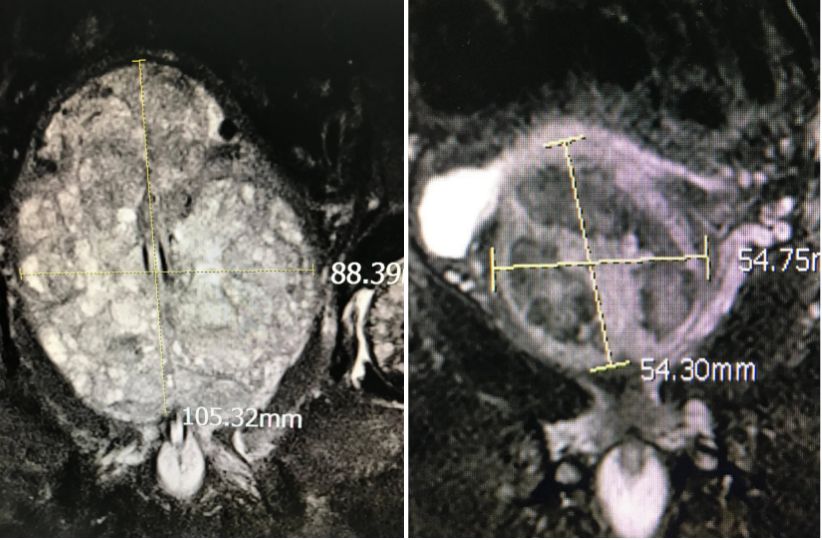

圖:通過栓塞增生部分萎縮(圖為栓塞前和栓塞后一個月的對比)